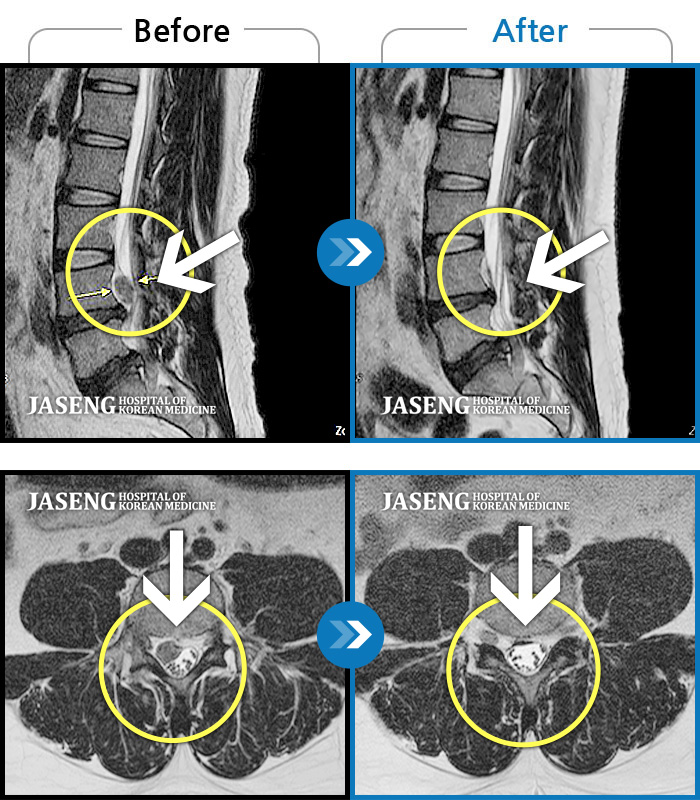

MRI 치료사례

허리디스크로 인한 양측 허리 통증